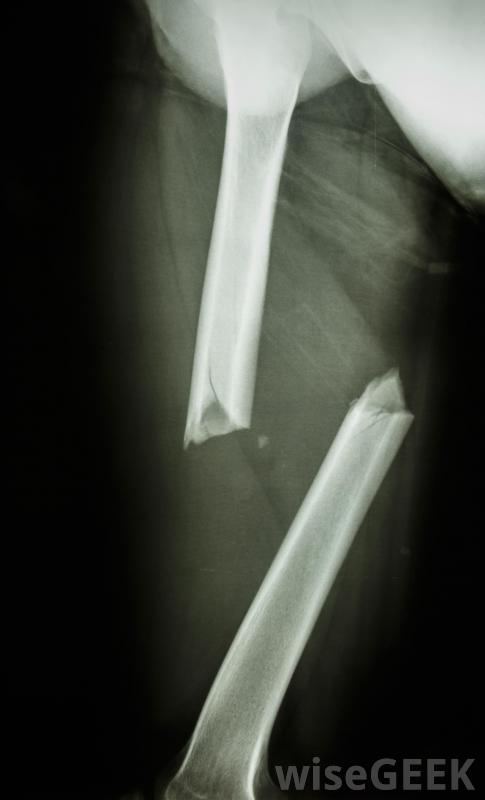

X光片将显示骨头骨折的严重程度由于骨折的严重程度通常与阻生性骨折有关,这种情况通常会给患者带来大量的疼痛。尽管疼痛程度因人而异,且随着损伤程度的不同,但疼痛往往是痛苦的为了控制这种程度的疼痛,医生可能会建议使用止痛药。止痛药的种类可能取决于病人的不适程度;非处方药如非甾体抗炎药对一些人来说可能足够了,而其他人可能需要处方

严重的撞击骨折通常需要使用钢板、杆和螺钉来重新对齐骨骼损伤不太严重,固定可能足以治疗。医生通常会用X光片、核磁共振成像或CT扫描来检查骨折的严重程度和碎片的位置。较轻的骨折可以用夹板、吊索固定,或石膏,使受影响的区域保持不动。这样可以防止骨头的末端互相摩擦或进一步相互推进,并使骨头愈合。可能有必要在相当长的时间内尽量减少受伤区域的移动,即使在取出石膏或夹板之后,因为撞击骨折通常愈合得很慢